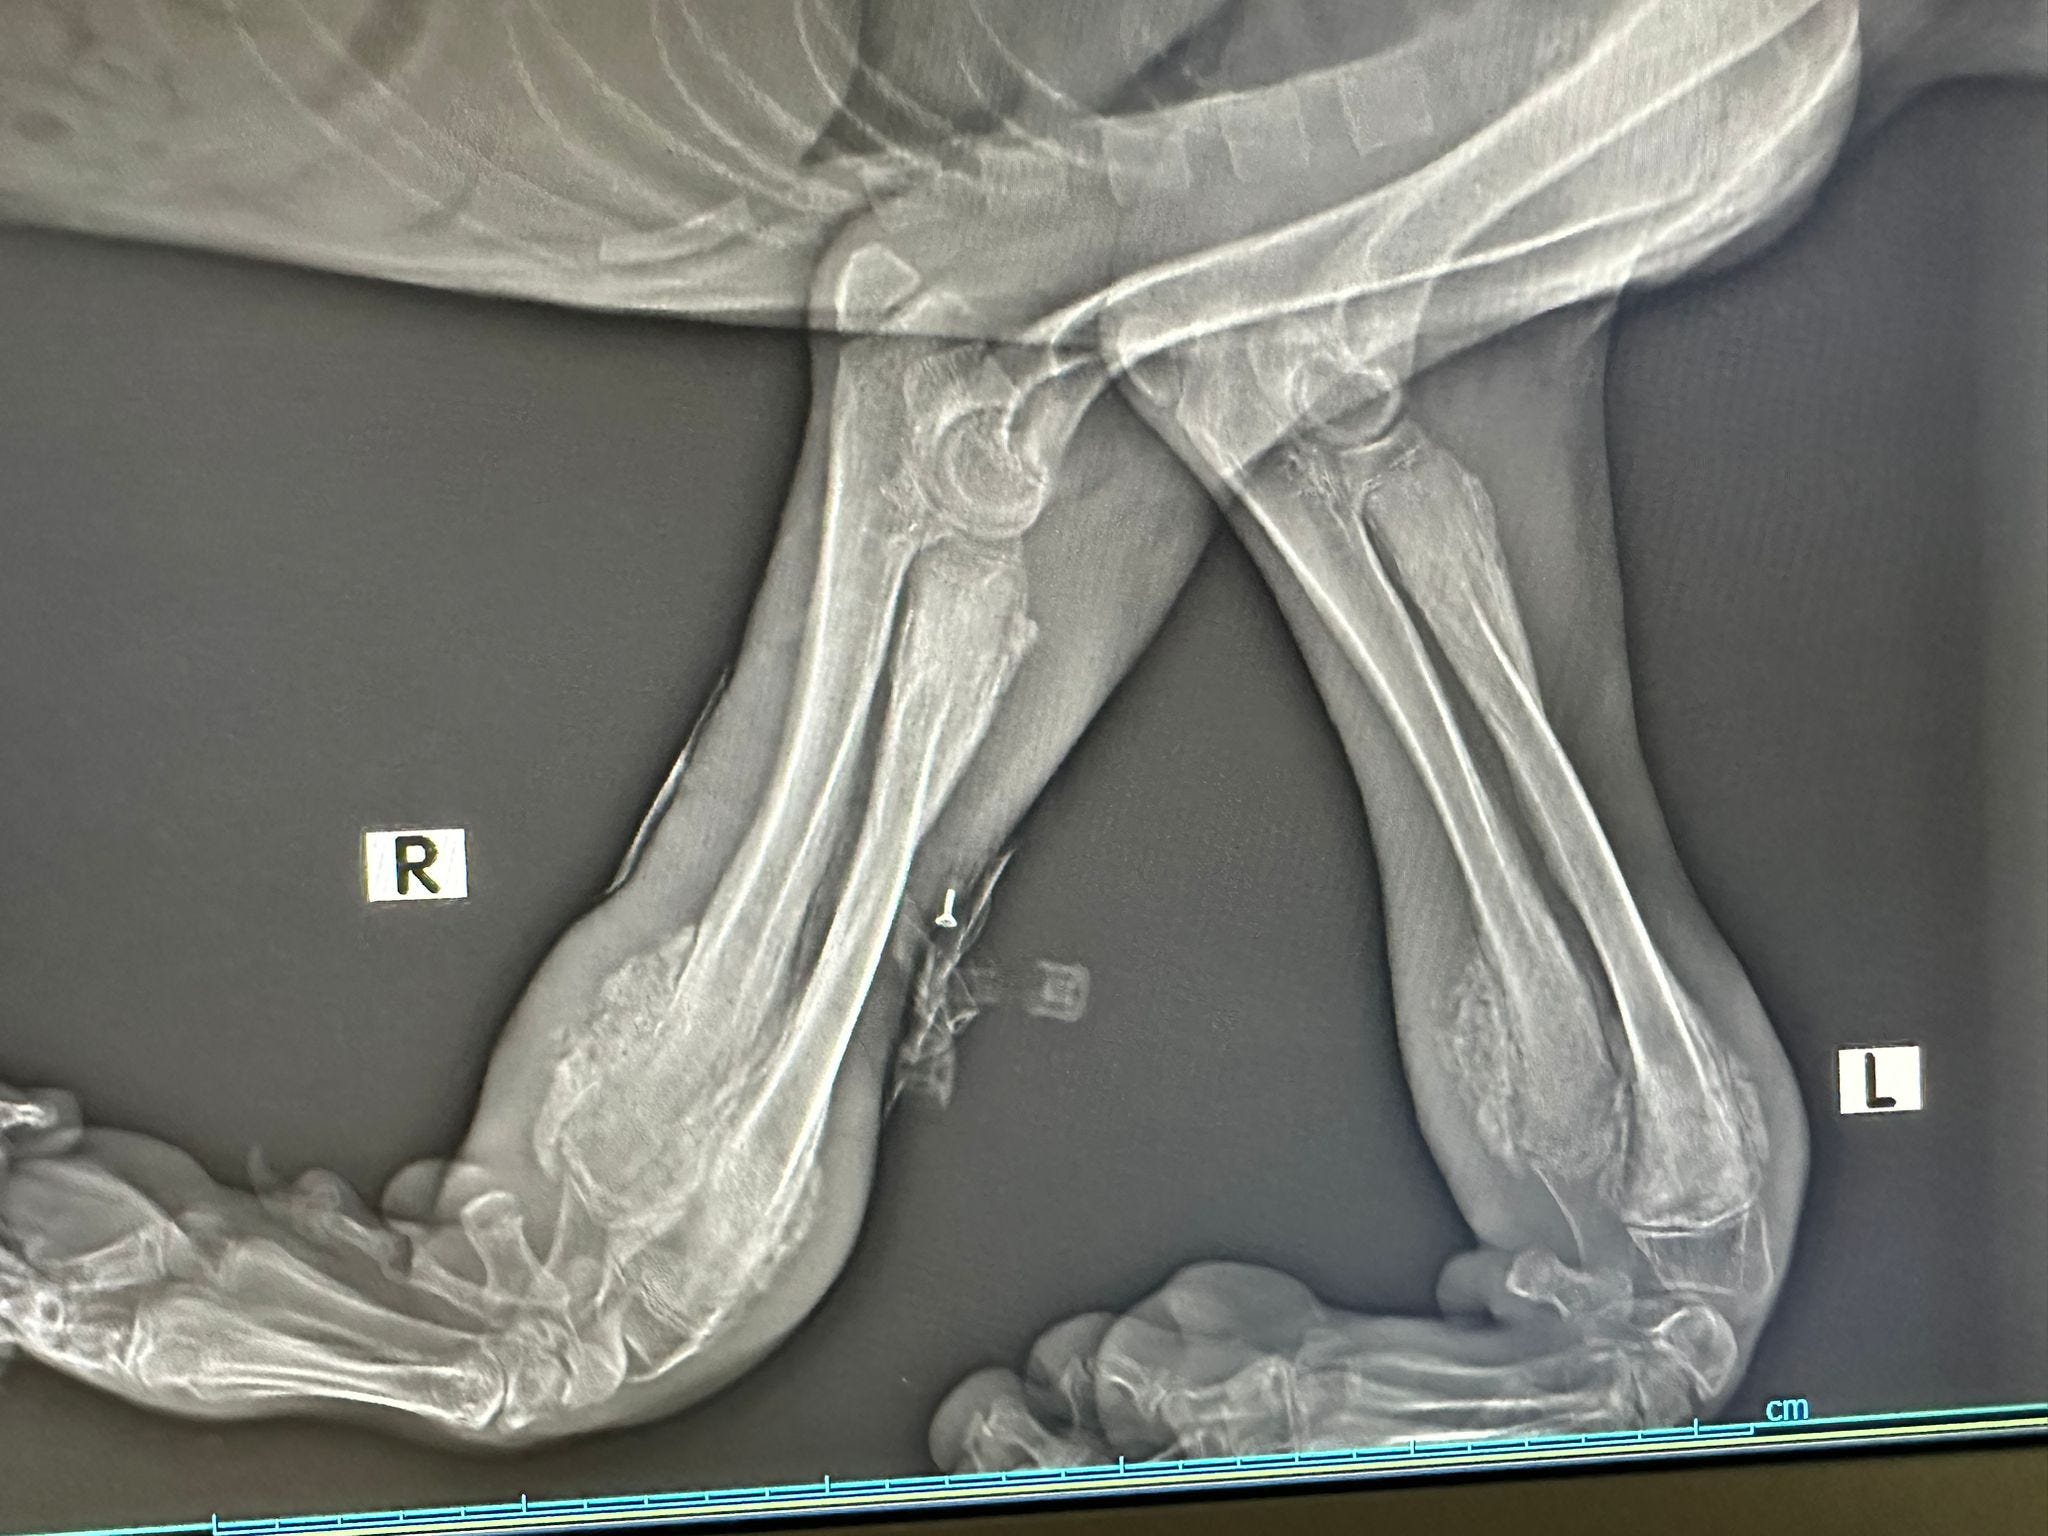

The stiffness in Milo’s leg, which we mentioned earlier, was eventually traced to a failed surgical plate.

Sadly, while not common, plates can sometimes fail, and in Milo’s case it caused further complications. A replacement plate was fitted, but damage to the surrounding muscle from the original procedure meant that his recovery was severely hindered.

For months, Milo struggled to carry the useless limb, which was clearly slowing him down and preventing him from thriving. After much thought and discussion, we made the difficult but compassionate decision to amputate.